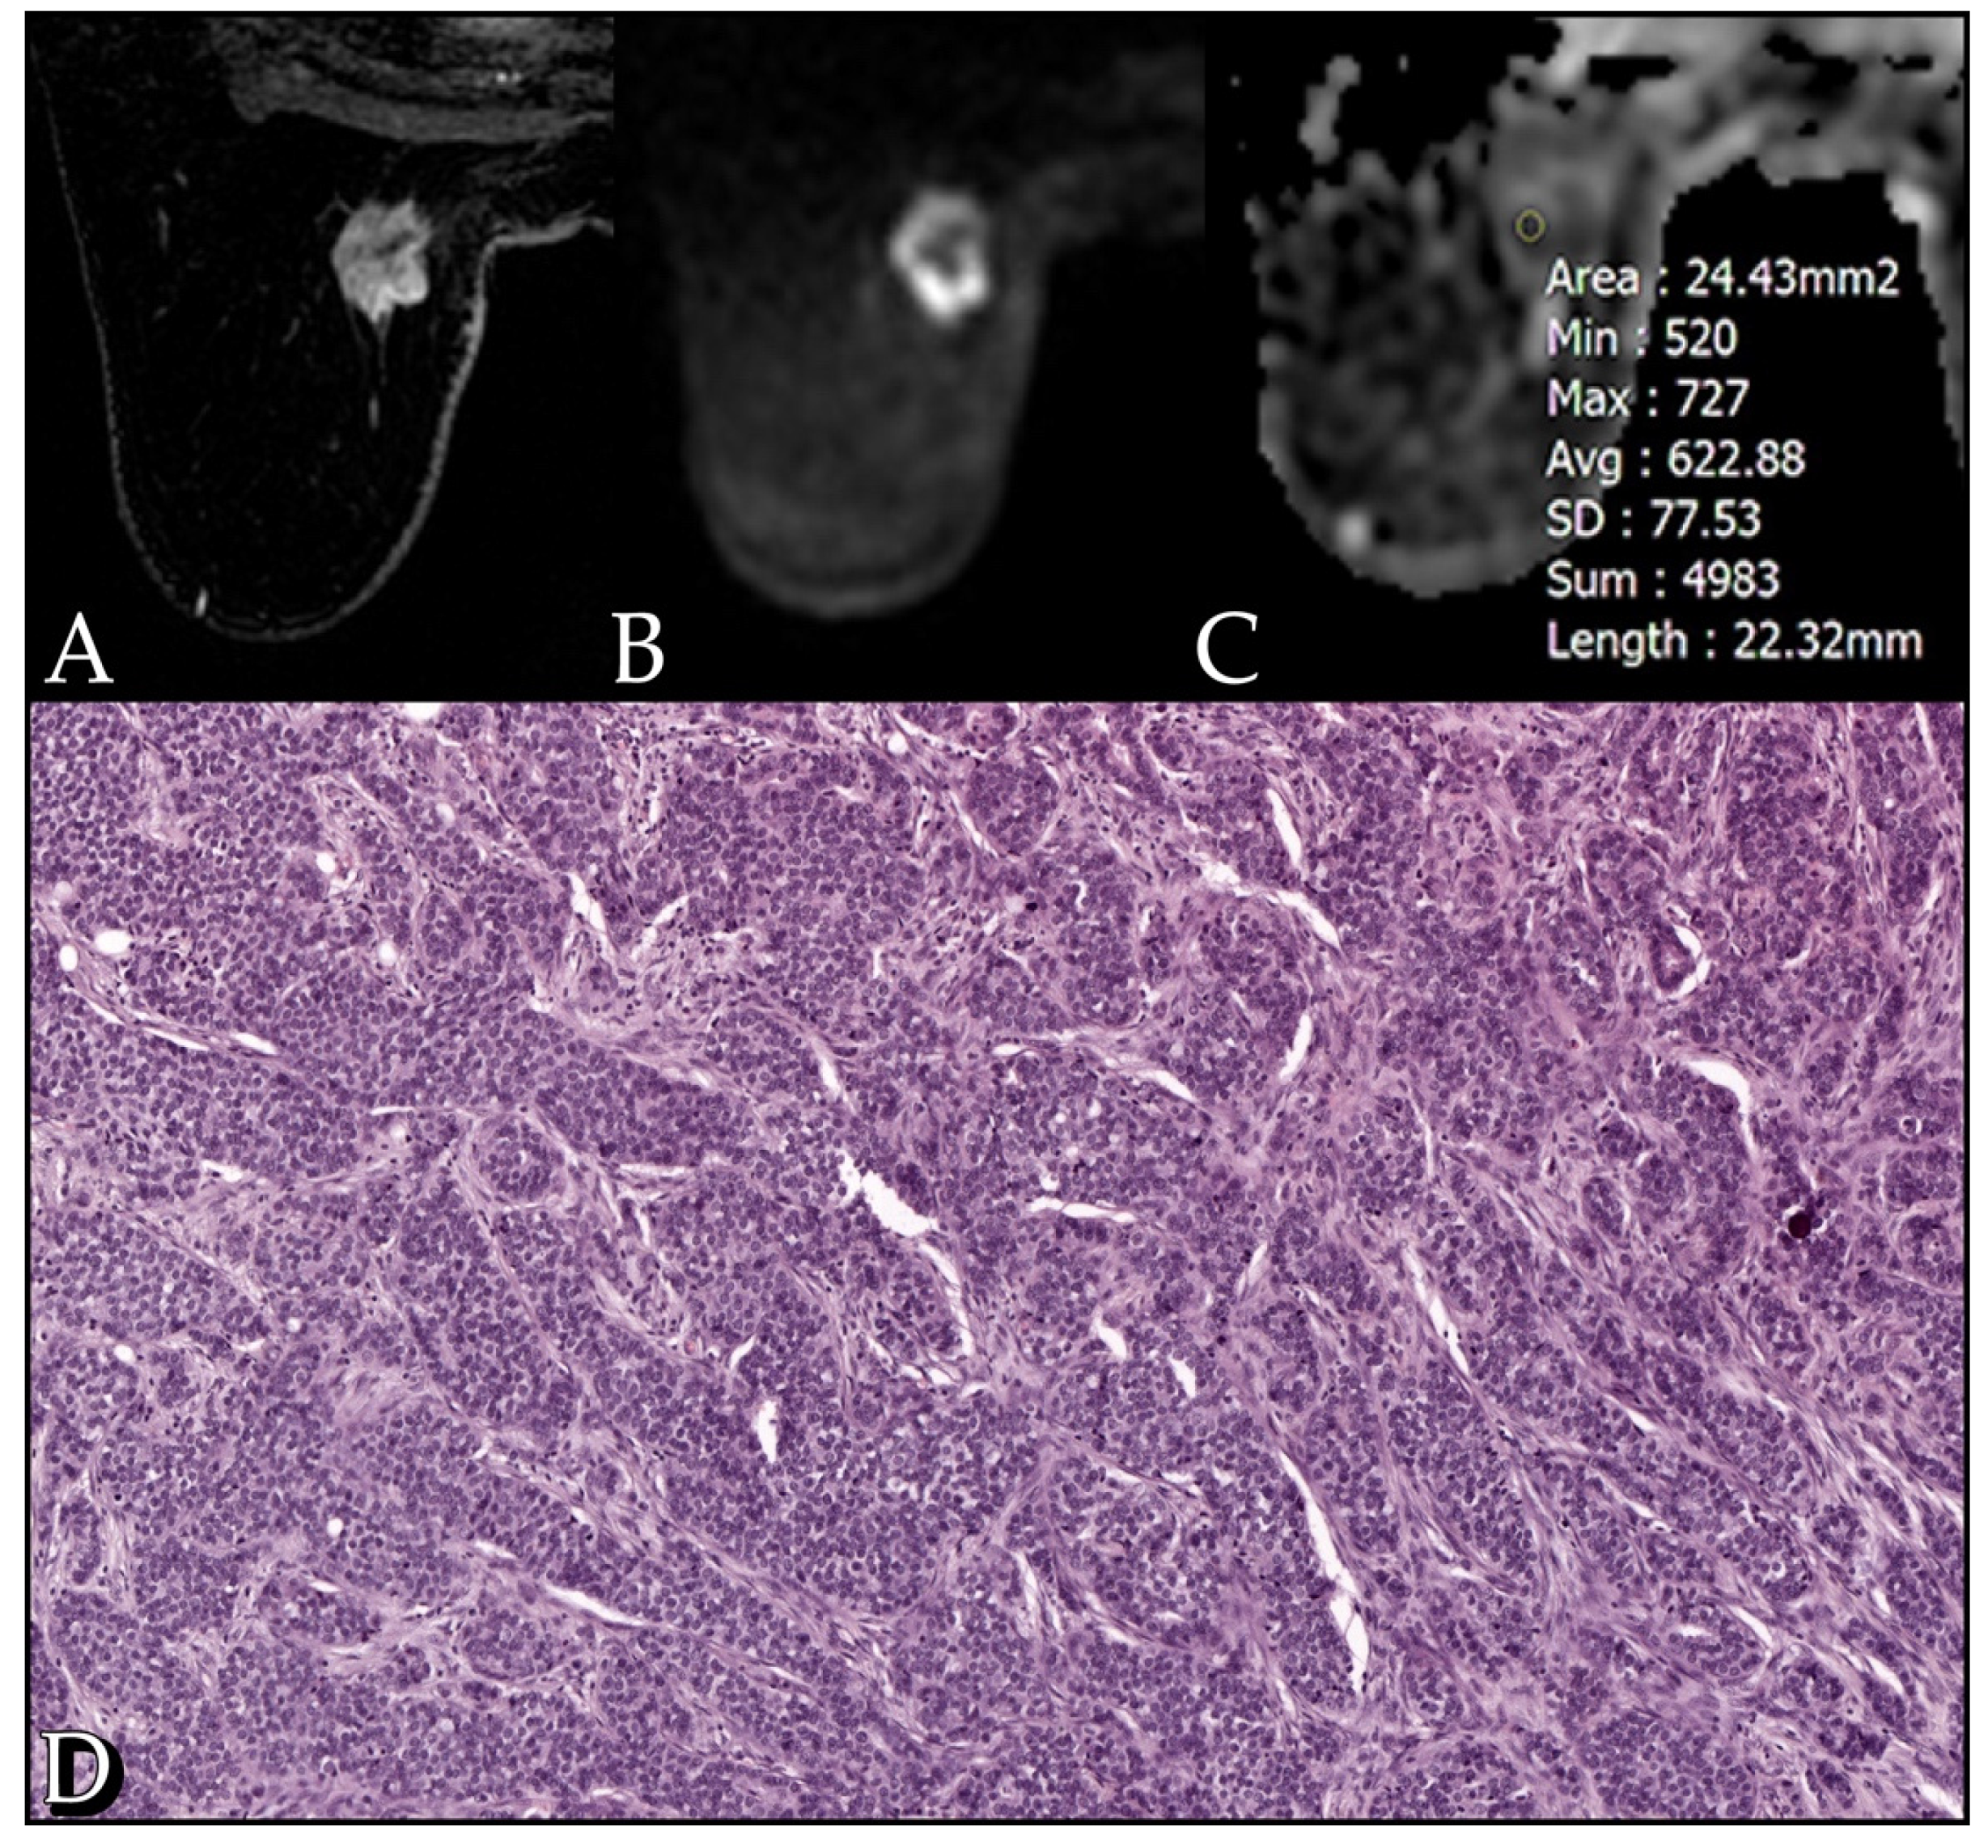

3. Results